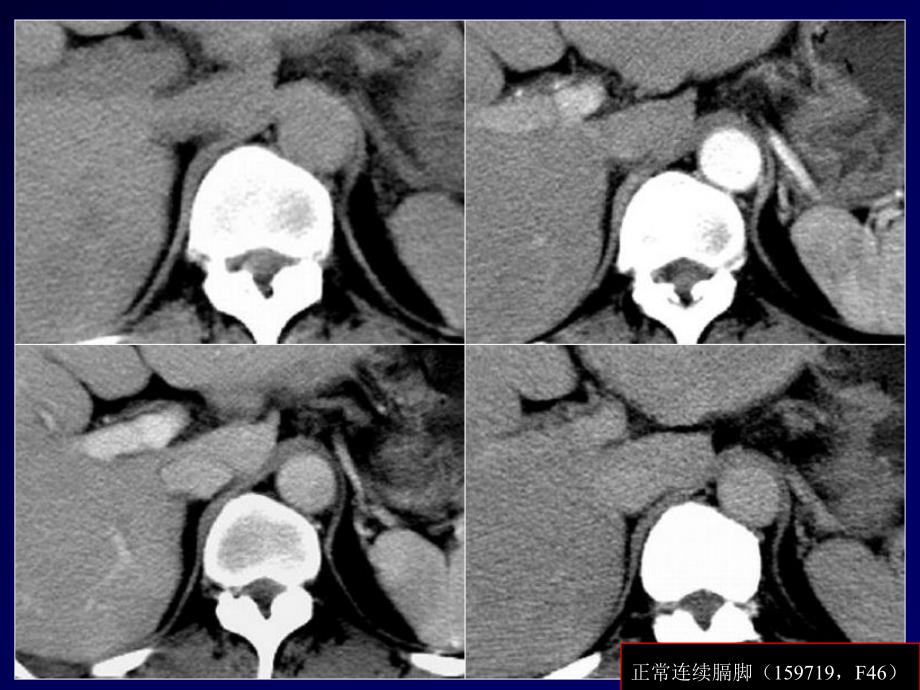

正常连续膈脚(159719,F46)正常连续膈脚(66009):T1WI较低信号,T2WI低信号,增强扫描无明显强化。膈脚不均匀肥厚(202300,M57):平扫密度比血管高,增强扫描呈缓慢轻度强化。膈脚不连续(189701,M41)多结节膈脚(158229)膈脚(80875,M32):结节状膈脚易误为肿大淋巴结。膈脚(183833,M40):误为肾上腺增生。膈脚(186619,F80):结节状膈脚易误为肿大淋巴结。膈脚(205030,M45):结节状膈脚易误为肿大淋巴结。膈脚(186939,M60):同一次检查,不同呼吸状态扫描,膈脚形态不同。膈脚(205540,F70):同一次检查,不同呼吸状态扫描,膈脚形态不同。膈脚分叉(204845,M65)